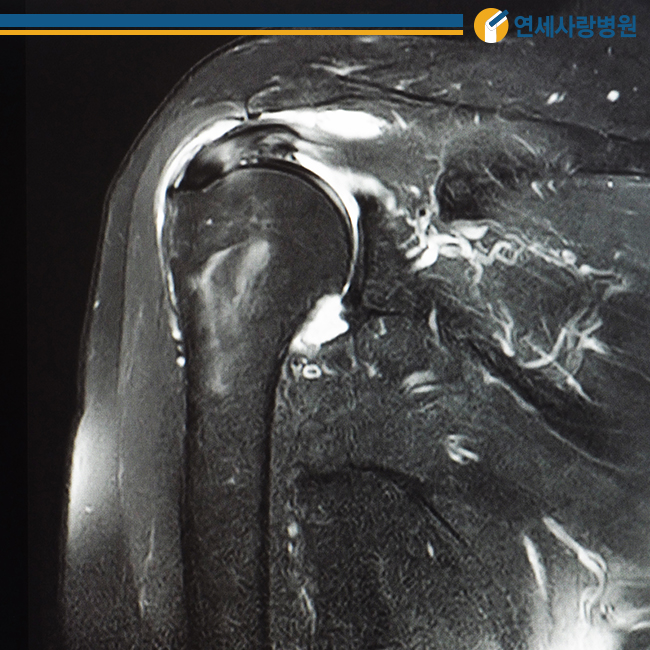

관절낭은 팔 위와 어깨 관절을 얇고 넓게 감싸 움직임을 부드럽게 하는데, 여러 원인으로 인해 염증이 생기면 관절낭 자체가 매우 두꺼워지고 힘줄이나 인대가 유착되어 딱딱해집니다. 이때 발생하는 통증을 오십견이라고 합니다.

50대 전후로 많이 발생한다고 해서 오십견이라고 불리고 있습니다만, 정확한 명칭은 동결견 또는 유착성 관절낭염이라고 불립니다. 어깨를 움직이는 데 제한이 있을 뿐만 아니라 어깨 관절을 움직이려고 해도 더 이상 움직일 수 없기 때문에 주의가 필요합니다.